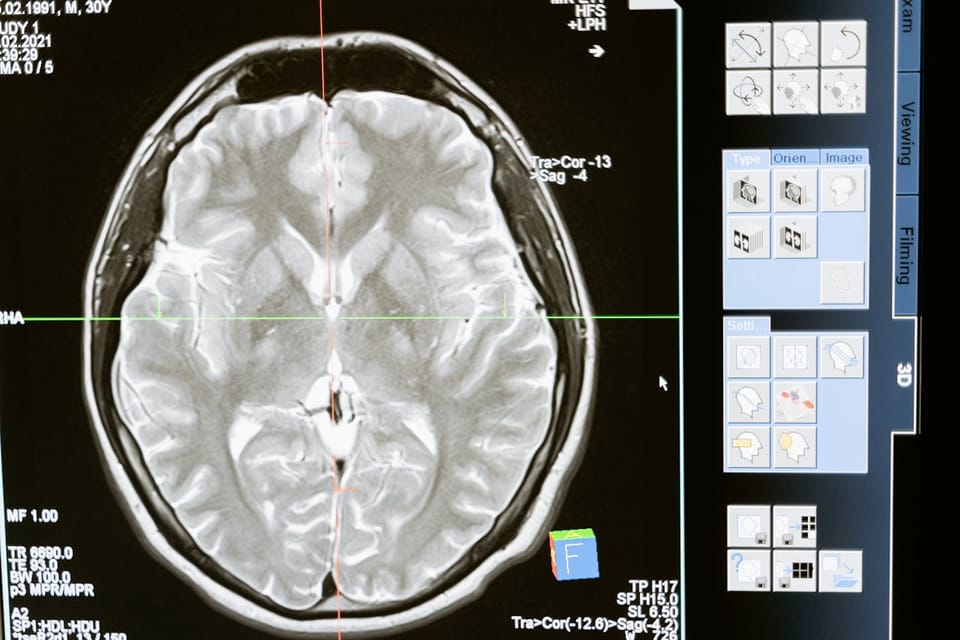

They are indispensable in radiology, particularly in X-ray, MRI, and CT scan machines. These devices rely on high-contrast, high-resolution displays to produce detailed images, and monochrome LCDs provide the necessary clarity to distinguish between subtle differences in tissue density and structure, which is vital for identifying fractures, tumors, and other anomalies. The improved image quality helps radiologists interpret results accurately resulting in better diagnoses and improved patient outcomes.